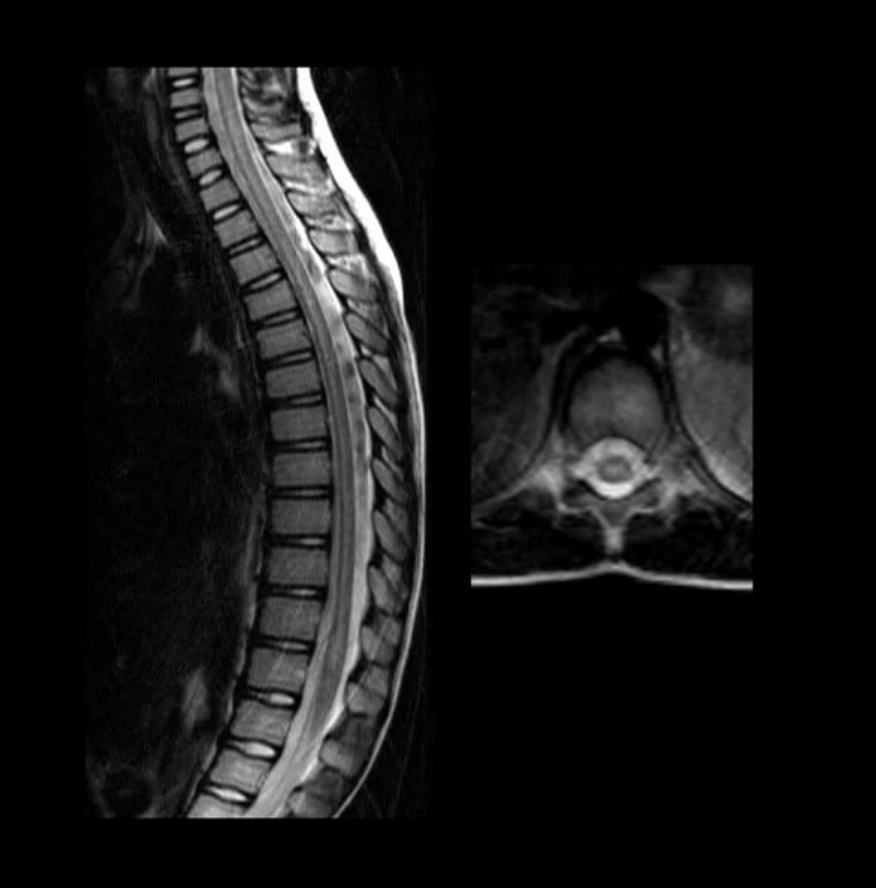

- Chụp cộng hưởng từ (MRI). Chụp MRI có thể cho thấy tình trạng viêm tủy sống. Và có thể phát hiện các nguyên nhân tiềm ẩn khác gây nên triệu chứng. Có thể kể đến như các bất thường tại tủy sống hoặc mạch máu.